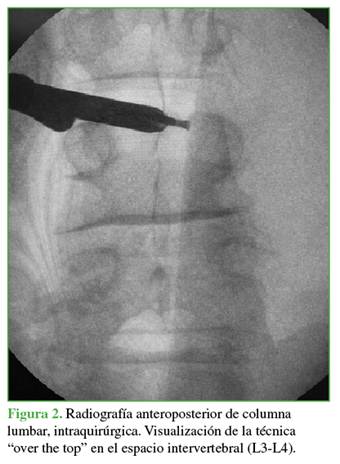

Los hallazgos fueron consistentes con un quiste sinovial facetario hemorrágico. Dados la presentación aguda con déficit neurológico motor progresivo y el severo compromiso radicular, el paciente fue sometido de urgencia a una descompresión. El objetivo fue aliviar la compresión neural, revertir el déficit motor y permitir una recuperación funcional rápida, minimizando la invasividad. Se optó por una descompresión endoscópica uniportal interlaminar posterior, utilizando un abordaje contralateral (izquierdo) y la técnica “over the top” (por encima del saco dural) para resecar el quiste de forma segura y completa (Figuras 2-5).

El abordaje interlaminar contralateral (“over the top”) fue el pilar de nuestro éxito. Esta técnica, recomendada para lesiones mediales y quistes en niveles lumbares bajos con espacio interlaminar adecuado,9 nos permitió resecar todo el quiste desde un ángulo seguro y ergonómico, preservando por completo la integridad de la hemicápsula facetaria contralateral (sintomática). Esto es una ventaja decisiva frente a un abordaje transforaminal, que podría haber sido insuficiente para un quiste de este tamaño y esta localización, o un abordaje directo, que hubiera comprometido la estabilidad facetaria del lado afectado.10